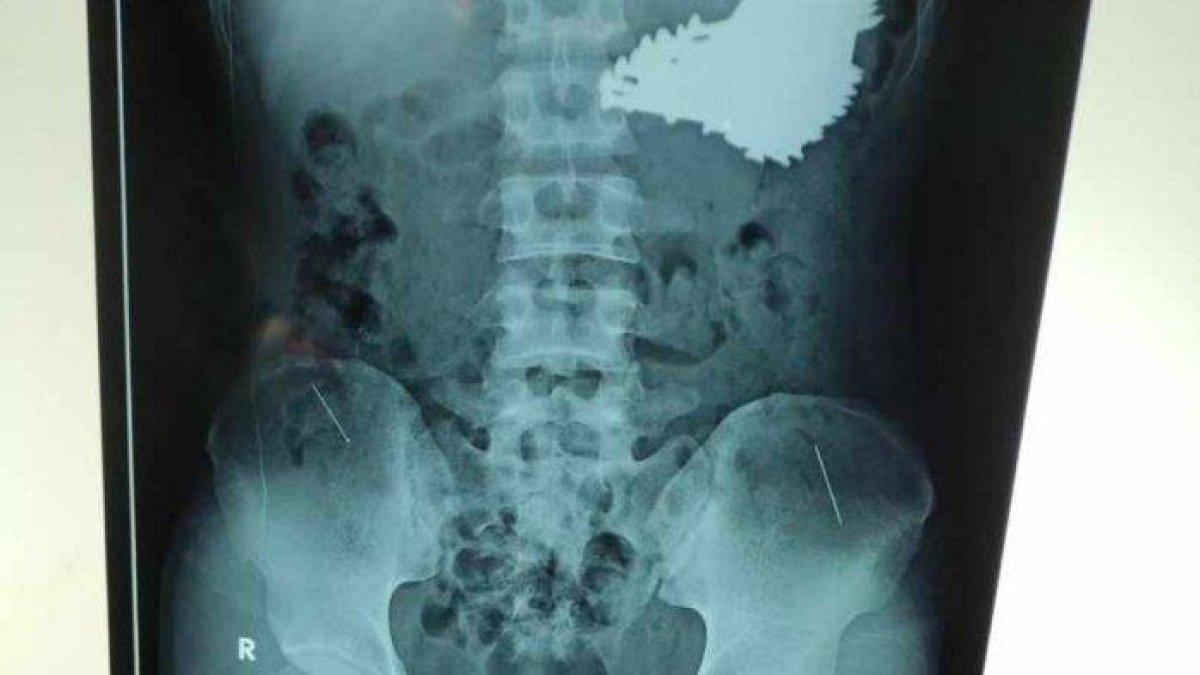

5 Fakta Mencengangkan 70 Paku Bersarang di Perut Pemuda di Indramayu, Jabar: ODGJ & Overdosis Obat

Inilah lima fakta mencengangkan kasus 70 paku yang bersarang di perut seorang pemuda di Indramayu, Jawa Barat yang diduga ODGJ & overdosis obat.

5 fakta mencengangkan kasus 70 paku yang bersarang di perut seorang pemuda di Indramayu, Jawa Barat yang diduga ODGJ & overdosis obat.

Operasi pengangkatan paku dari tubuh pemuda asal Indramayu itu memang berhasil dilakukan.

Tapi yang mengagetkan, beberapa butir paku di antaranya ditemukan sudah dalam kondisi berkarat.

"Kondisinya pada saat itu memang sudah berkarat dan kondisinya sudah berkumpul menjadi satu di dalam lambung," ucap Deden.